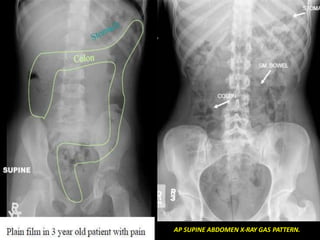

AP SUPINE ABDOMEN X-RAY GAS PATTERN.

•Colon has sacculations called

haustra as teniae coli are

shorter than the colonic wall

•Colon is relatively peripheral

but can be very mobile

Reading the AbdominalPlain Film. • Also known as the “KUB” (kidney, ureter, & bladder). •Use a systematic approach to Interpretation. – Lung bases & diaphragms. – Bones. – Soft tissues. • Abnormal calcifications. • Organs. Stomach

AP SUPINE ABDOMENX-RAY GAS PATTERN.

•Colon has sacculationscalled haustra as teniae coli are shorter than the colonic wall •Colon is relatively peripheral but can be very mobile